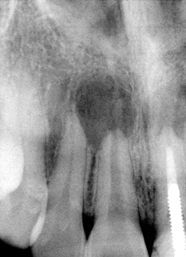

Remove #9,10 crowns, #9 lingual margin subgingival; pulpal test: #8,10 necrosis. Remove #9 post, redo RCT, #8, 10 RCT, #8,10 in office internal bleaching; #9 cast post, ortho extrusion before #9,10 crowns